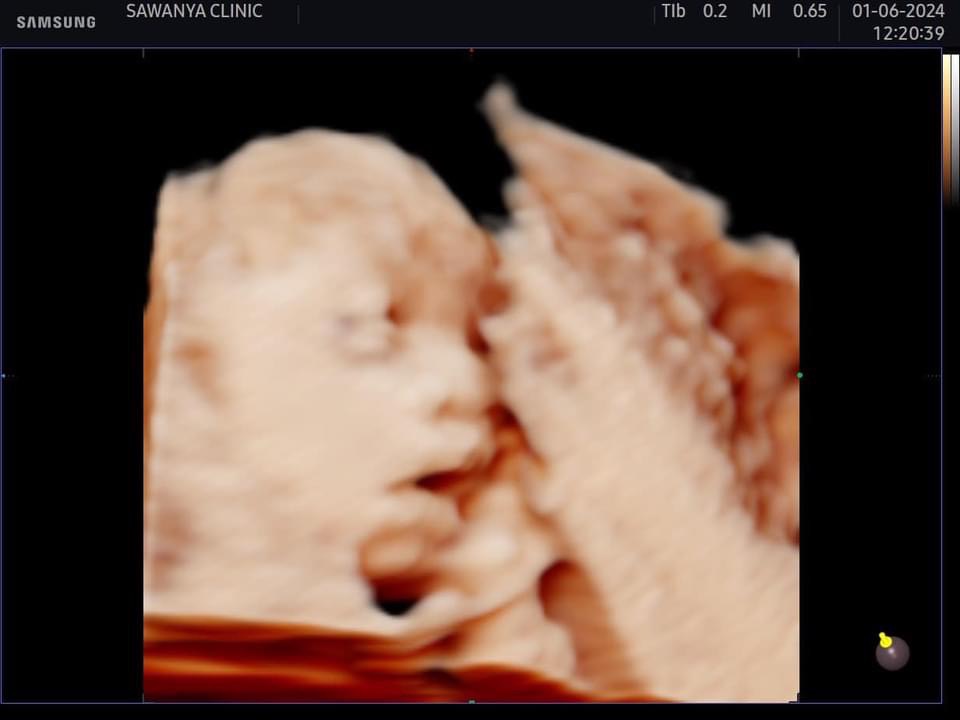

ทำเอาคุณแม่มือใหม่อย่าง ธัญญ่าอาร์สยาม ใจฟู ได้เห็นวิวัฒนาการของลูกใน 27 สัปดาห์

บอกเลยอะค่ะเตรียมตัวรับมือการเป็นคุณแม่ป้ายแดงที่จะได้เจอหน้าลูกในเร็ววันนี้ด้านธัญญ่าตื่นเต้นเตรียมของต้อนรับสมาชิกใหม่ไวให้ลูกเต็มบ้าน และ คอยอัพเดทผ่านโซเชียลให้กับบรรดาเอฟซีแฟนคลับได้ลุ้นรอเชียร์กันไปตามตามกันแล้วค่ะ